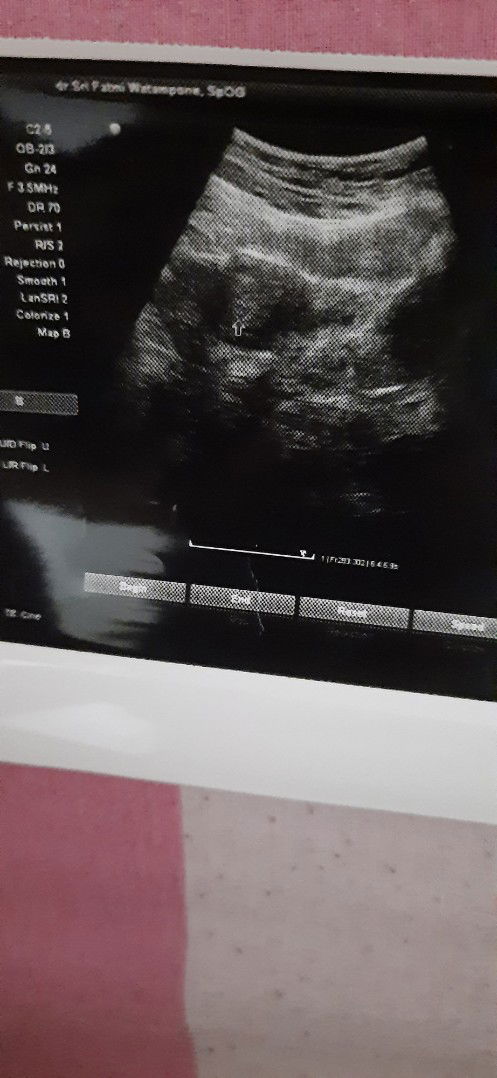

test pack negatif namun ada kantong kehamilan

Menurut moms, waktu di USG ada penampakan kantong kehamilan kok di testpack selalu negatif ya moms?